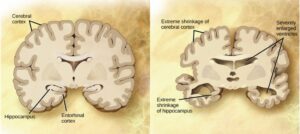

Figure 16.30. Compared to a normal brain (left), the brain from a patient with Alzheimer’s disease (right) shows a dramatic neurodegeneration, particularly within the ventricles and hippocampus. (credit: modification of work by “Garrando”/Wikimedia Commons based on original images by ADEAR: “Alzheimer’s Disease Education and Referral Center, a service of the National Institute on Aging”)

Drawing comparing how a brain of an Alzheimer disease patient is affected to a normal brain.

Alzheimers disease progression-brain degeneration.

Alzheimers entorhinal cortex.